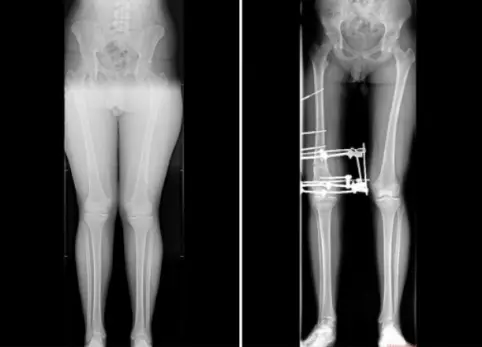

16-летний подросток страдал от вальгусной деформации - она вызывала сильную боль в коленях и вынуждала отказываться от занятий спортом. Кроме того, его смущал внешний вид ног.

На помощь пришли врачи Клиники СамГМУ. Ситуация оказалась непростой: деформация имела асимметричный характер, а одну из конечностей требовалось немного удлинить. Медики приняли решение проводить коррекцию поэтапно: сначала прооперировать одну ногу, потом вторую.

В начале декабря юноше сняли аппарат внешней фиксации. Сейчас он уже проходит реабилитацию и постепенно возвращается к обычной жизни. По словам врачей СамГМУ, без лечения у подростка мог развиться артроз коленного сустава.